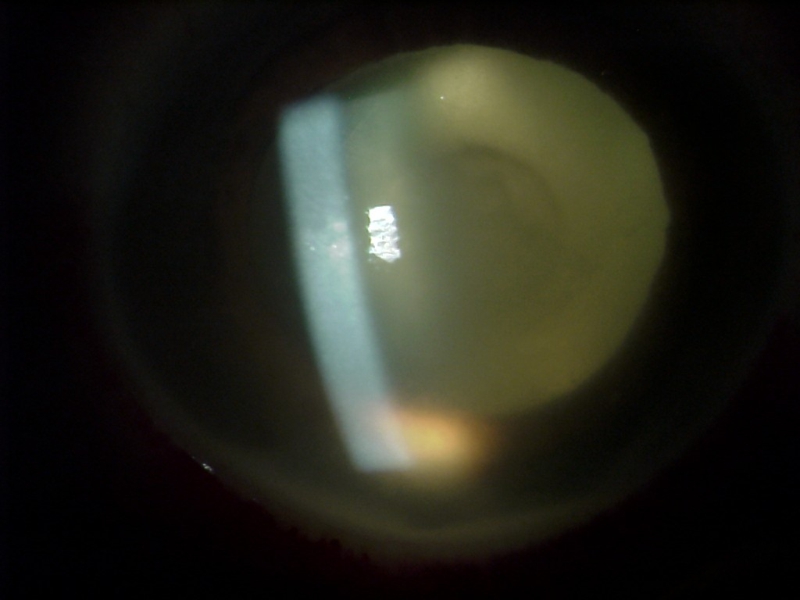

El hipopion (Figura 2) puede estar presente hasta en un 85.7% y su evolución en las primeras horas puede orientarnos sobre la severidad del cuadro. También se pueden ver mallas de fibrina en área pupilar (Figura 3), que se dirigen en ocasiones hacia la incisión y la paracentesis y ante las cuales debemos realizar el diagnóstico diferencial con las uveítis postquirúrgicas del paciente diabético. Se puede observar edema corneal epitelial y/o estromal (Figura 4), infiltrados (pudiendo provocar incluso melting corneal), defectos epiteliales, abscesos en la zona de los puntos corneales, etc..

En casos iniciales se puede observar células blanquecinas en vítreo anterior, que suele evolucionar rápidamente hacia vitritis densa que nos hará difícil valorar detalles retinianos o frecuentemente no se ve ningún detalle simplemente un reflejo amarillento-blanquecino, signo de gravedad severa (Figura 5). En casos en los que la vitritis no es muy severa es posible observar hemorragias intraretinianas en semiperiferia así como periflebitis, hallazgos que en la fase más precoz puede ayudar a orientar el cuadro de endoftalmitis infecciosa12.

Figura 2. Hipopion.

Figura 3. Malla de fibrina en el área pupilar.

Figura 4. Edema corneal asociado a endoftalmitis.

Figura 5. Vitritis densa.